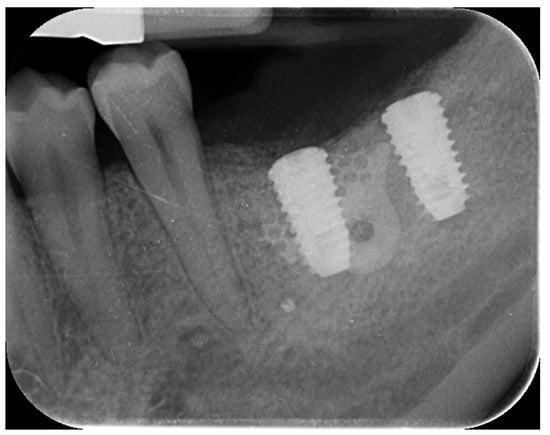

A 44-year-old female patient presented with pain and swelling in the left mandibular region, primarily motivated by functional concerns and a desire to improve periodontal health. The patient reported the placement of a dental implant six years earlier in the region of the left mandibular first molar, which had replaced a hopeless tooth (Figure 1).

Figure 1. Initial radiographic assessment showing peri-implantitis on the implant and periodontal involvement on the second left mandibular molar.